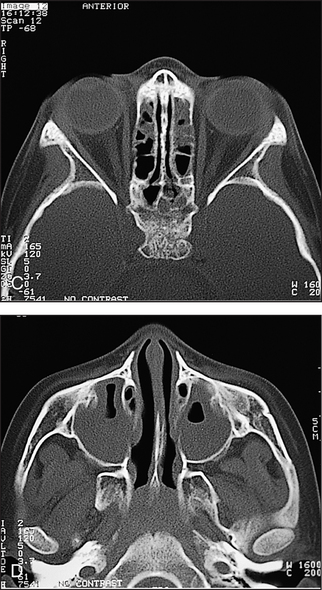

CT scans can be commonly used in the diagnosis of sinusitis and nasopharyngeal tumours. They can help identify the spread of infection into the brain and orbits (see Figures 38.27 and 38.28).

Figure 38.28 Acute sinusitis This CT scan coronal view shows opacification of the right maxillary sinus; the left is almost completely opacified, with only a small air pocket visible. (Zitelli, Davis. Atlas of pediatric physical diagnosis, 5th edn. Elsevier, 2007.)